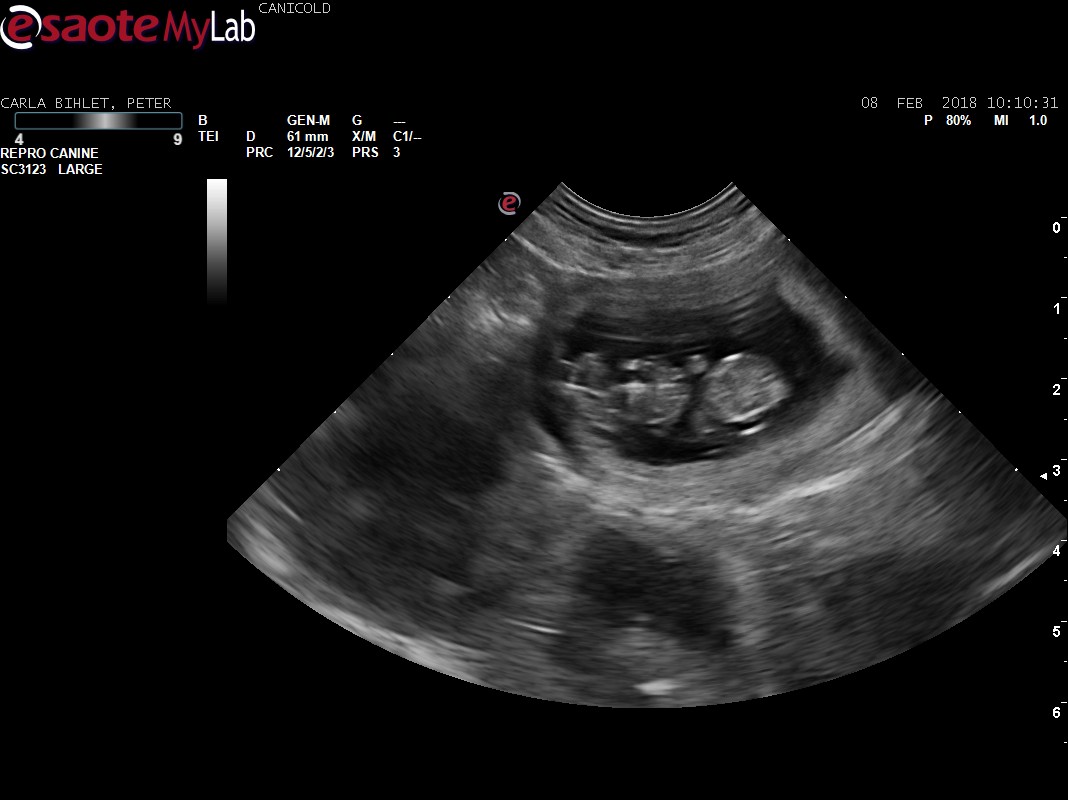

We did a pregnancy scan on Carla last week and luckily the trip to Holland was a succes. Carla is expecting puppies and the vet has set the due date at March 11th – needless to say we are very excited!! This will be our first litter in 10 years, the first litter of puppies our children will experience and our very first litter of PBGVs – so this is truly huge for us in many ways! ;o)